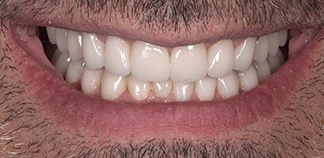

Результаты лечения пациентов

До лечения

Жалоба на отсутствие нормальных жевательных зубов.

Как лечили

Удалены корни разрушенных зубов. Установлены импланты, проведена художественная реставрация зубов.

Лечащий врач

БОЙКО Артемий Петрович